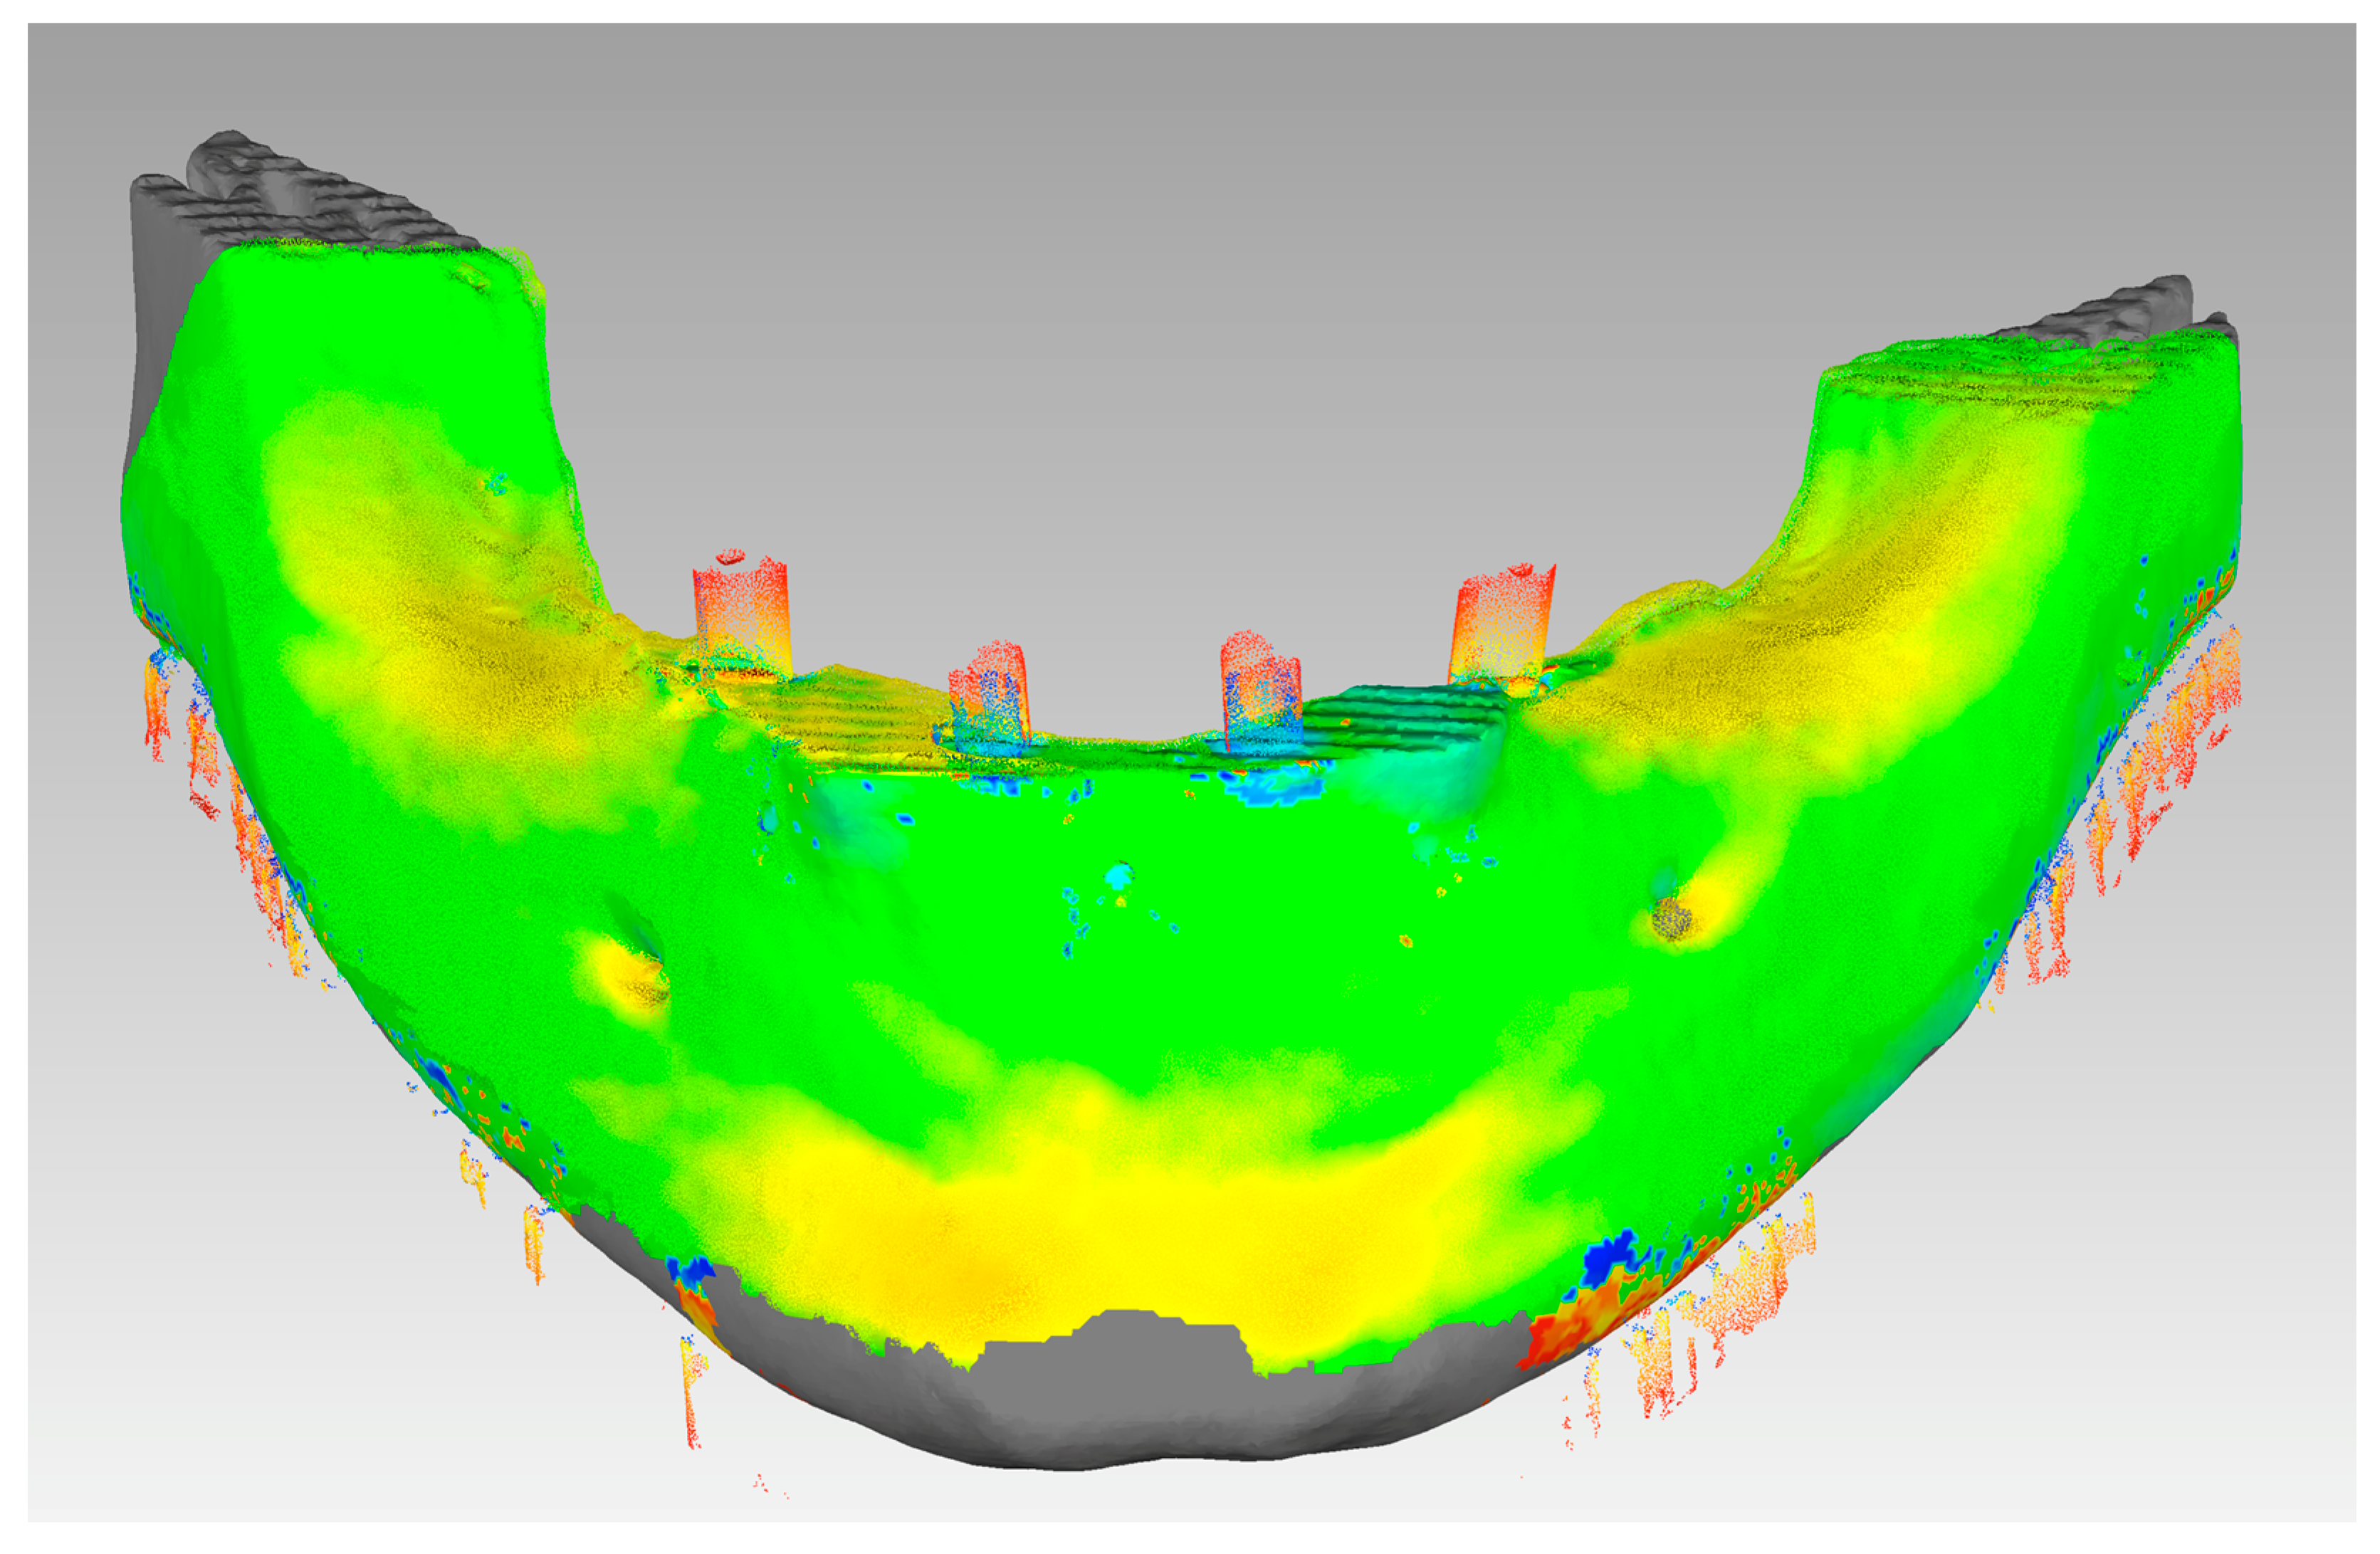

2. Materials and Methods

3.1. In Vivo Treatment Evaluation

3.2. In Vitro Treatment Evaluation